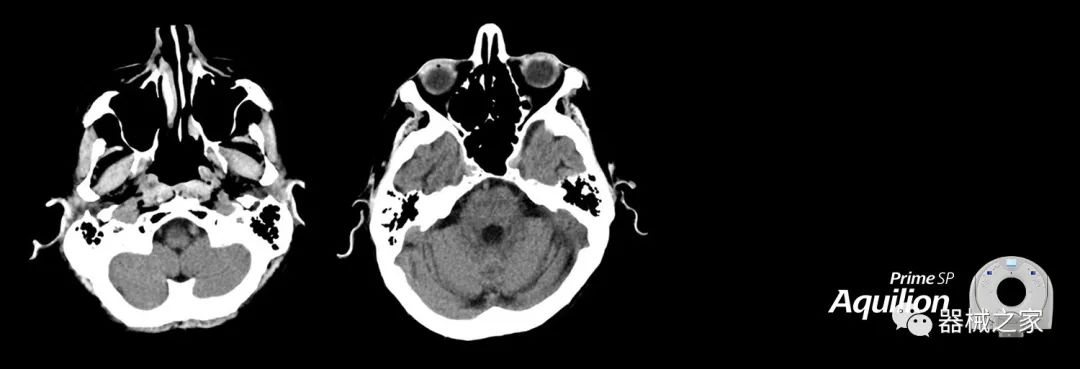

在以患者為中心的放射腫瘤學(xué)領(lǐng)域,計(jì)算機(jī)斷層掃描(CT)的可訪問性,可重復(fù)性和靈活性至關(guān)重要。為了建立這些價(jià)值,佳能醫(yī)療系統(tǒng)美國(guó)公司現(xiàn)在正在擴(kuò)大其放射腫瘤學(xué)CT模擬產(chǎn)品,包括Aquilion Prime SP和Aquilion Lightning 80高級(jí)CT系統(tǒng)。除了Aquilion LB之外,Aquilion Prime SP和Aquilion Lightning 80現(xiàn)在還包括放射治療(RT)選項(xiàng),可為腫瘤學(xué)規(guī)劃提供高質(zhì)量的CT成像和精密工具。

擴(kuò)展視野(EFOV)可以看到更多的解剖結(jié)構(gòu)。Aquilion LB采用85 cm EFOV,而Aquilion Prime SP和Aquilion Lightning 70采用70 cm EFOV。

Aquilion Prime SP使設(shè)施能夠處理具有挑戰(zhàn)性的案例,同時(shí)為員工提供快速,靈活和高效的解決方案。

兩個(gè)CT系統(tǒng)均采用0.5 mm x 80排PUREViSION探測(cè)器技術(shù)(可配置并從80-160現(xiàn)場(chǎng)升級(jí)),78 cm孔徑,50 cm視野,AIDR(自適應(yīng)迭代劑量減少)3-D和SEMAR(單個(gè))能量金屬神器減少)技術(shù)。